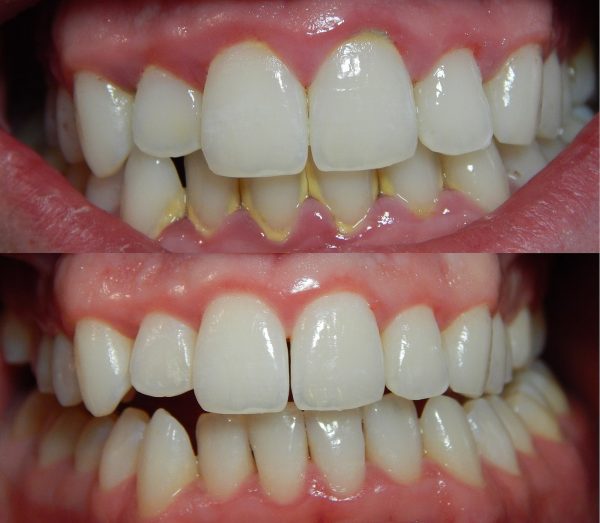

درمان های ژنژیویت

گرچه اگر بهداشت دهان و دندان در منزل به خوبی ادامه یابد، ژنژیویت معمولاً پس از یک پاکسازی تخصصی بهبود می یابد، اما باید هشدار داد که اگر بیمار در مراقبت های خانگی خود کوشا و دقیق نباشد و حداقل دو مرتبه در سال در پی پاکسازی تخصصی نباشد، این وضعیت به سرعت عود می کند.

دندانپزشک یا دستیار دندانپزشک برای پاکسازی، تمام پلاک ها و جرم های دندانی را طی فرآیندی به نام جرم گیری از بین می برد.

اگر ژنژیویت شدید باشد و جرم عمیقی وجود داشته باشد، بیمار ممکن است به چهار تمیز کردن عمقی (جرم گیری و تسطیح سطح ریشه) نیاز داشته باشد تا بافت لثه به وضعیت سالم باز گردد. علاوه بر این، دندانپزشک در مورد اصلاح دندان های نا همراستا یا پر شدگی ها، روکش ها یا بریج های نامناسب صحبت خواهد کرد.